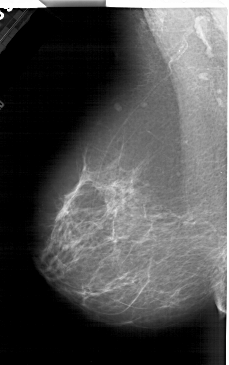

A_2001_1.RIGHT_CC

LEFT_MLO LINES 6196 PIXELS_PER_LINE 3886 BITS_PER_PIXEL 12 RESOLUTION 43.5 NON_OVERLAY